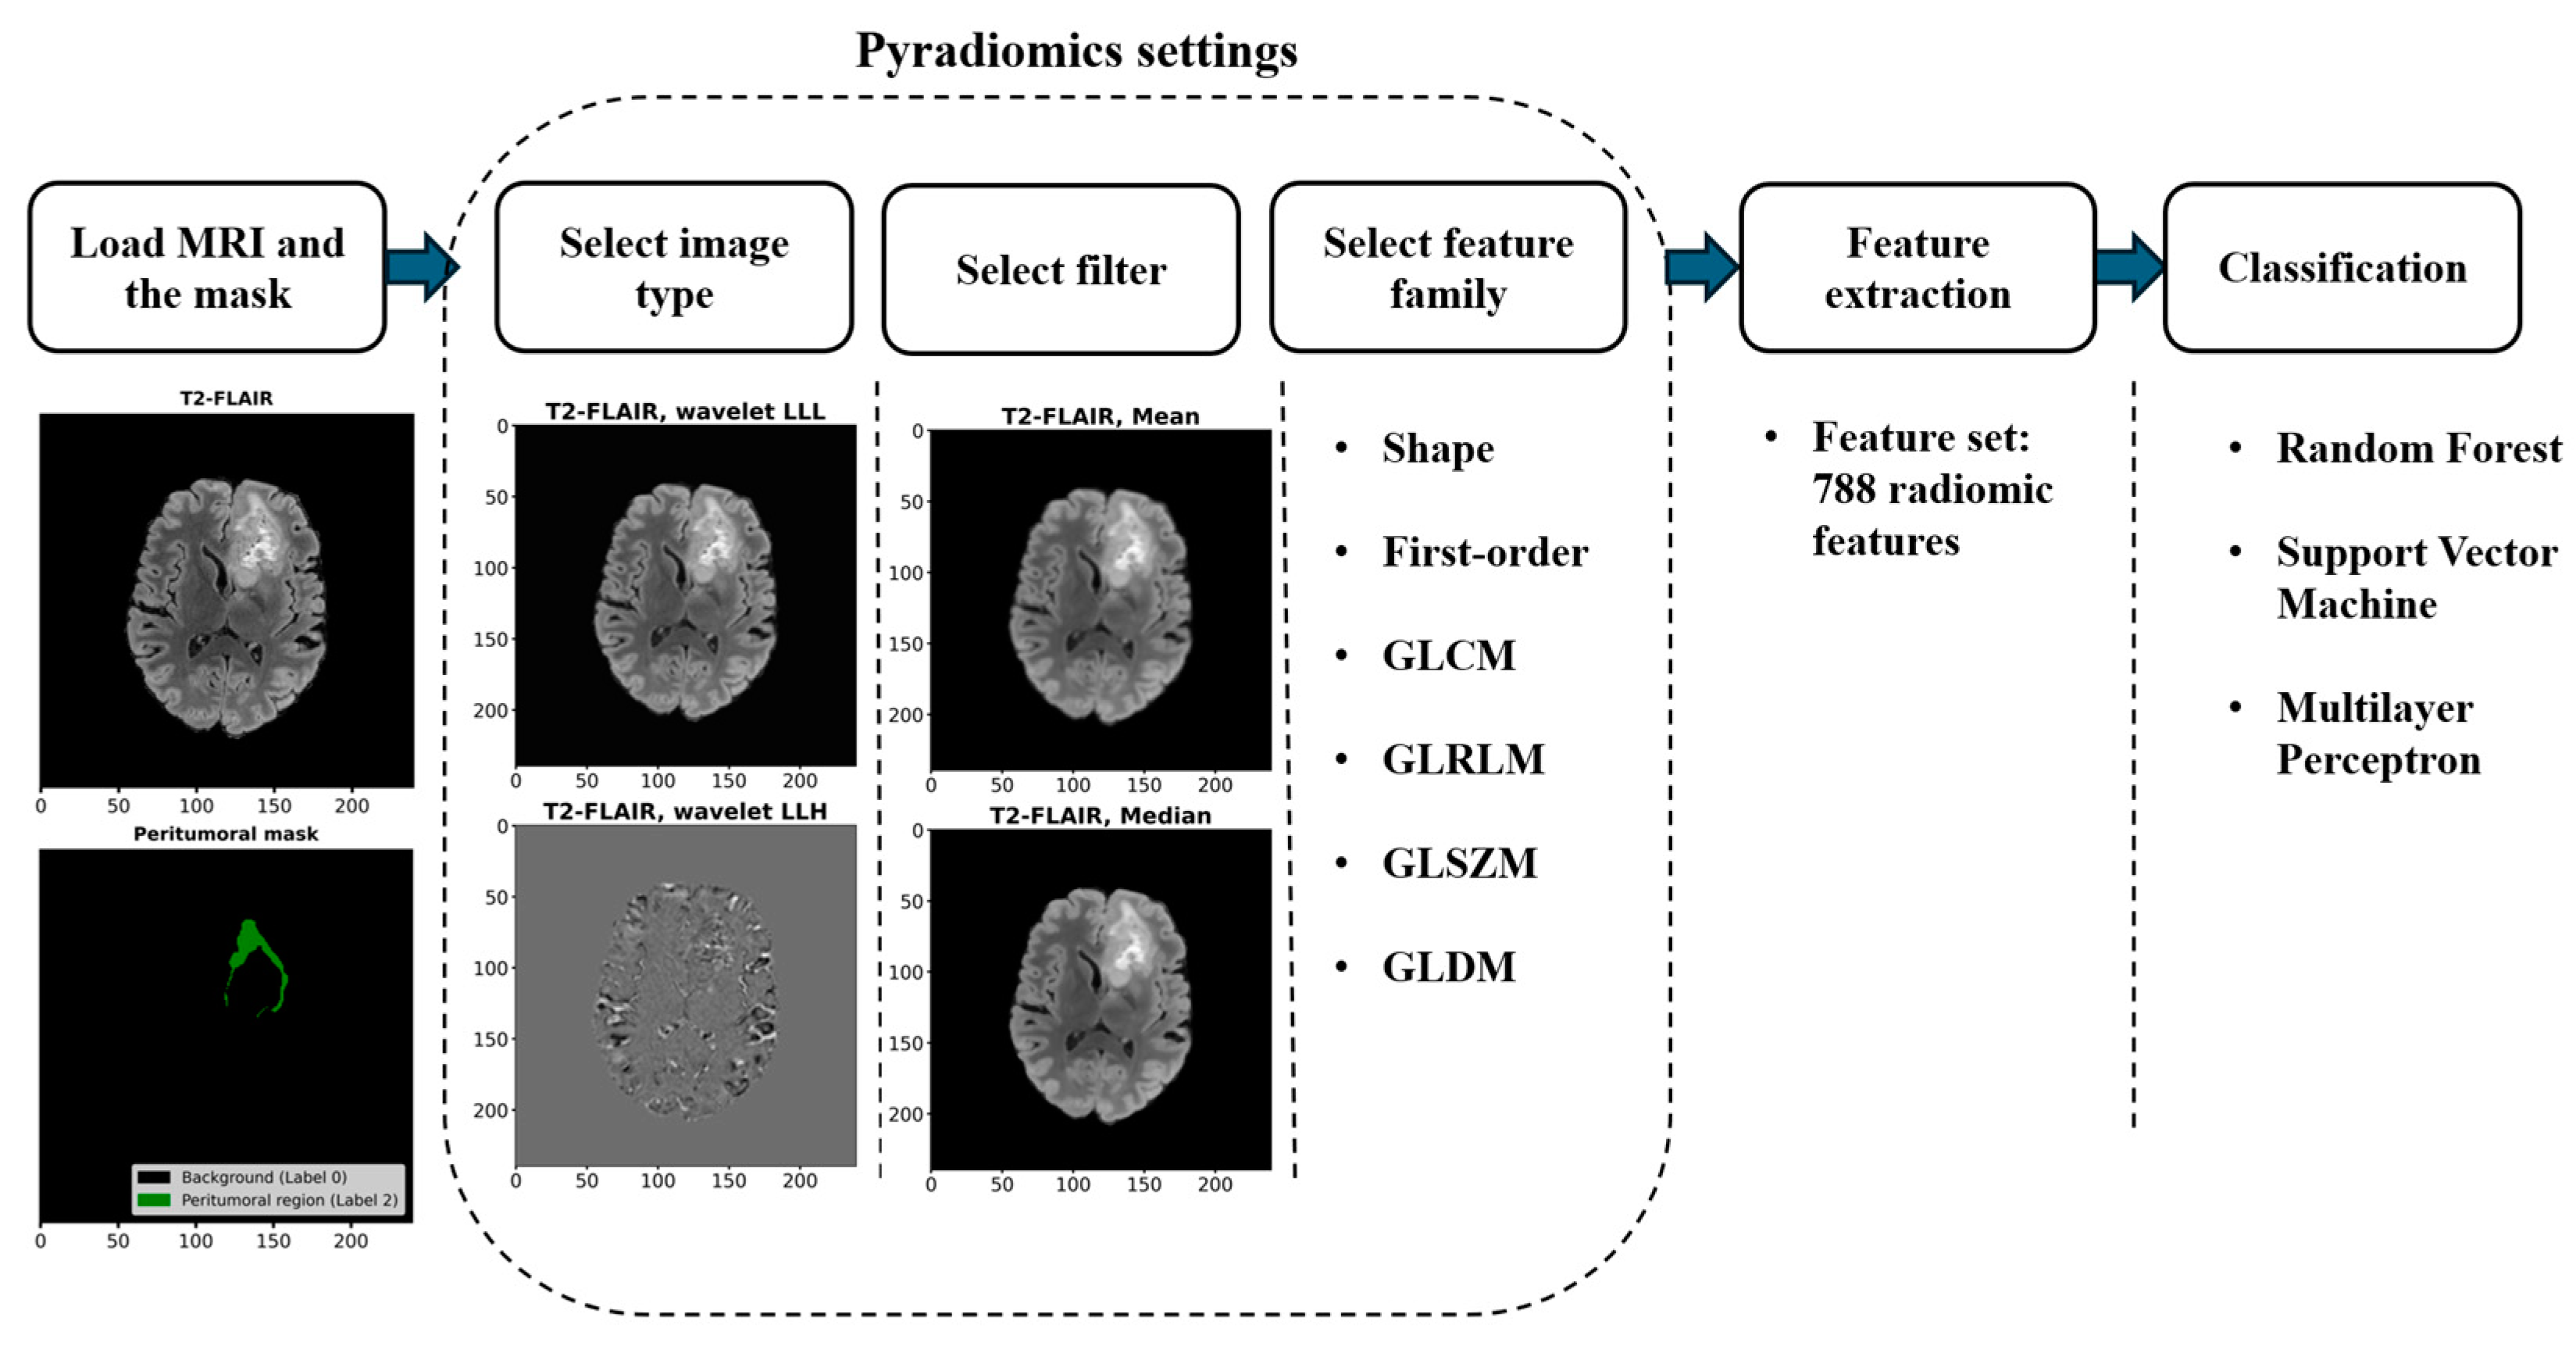

2.2.1. Workflow for Radiomic Feature Extraction and Tumor Classification

2.2.2. Radiomic Feature Extraction

2.2.3. Feature Normalization, Data Imbalance Handling, and Feature Selection

2.2.4. Classification and Performance Evaluation